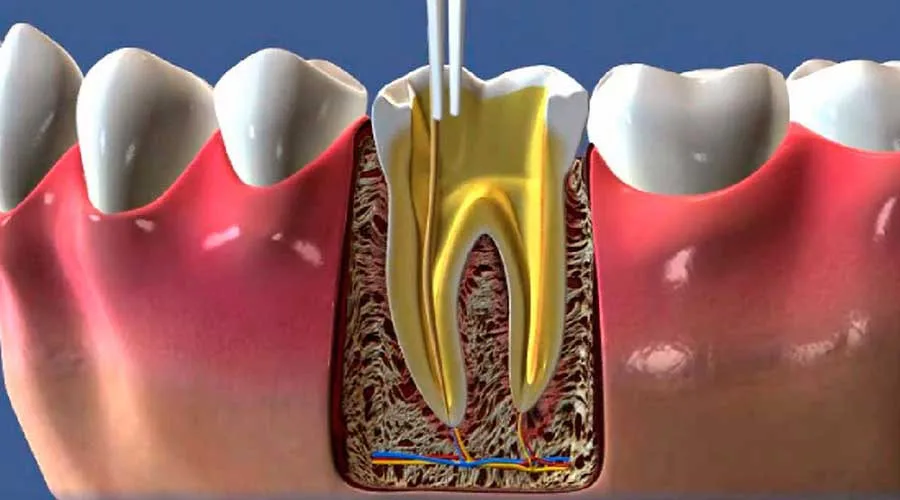

Com o suporte de profissionais qualificados, a endodontia promove um atendimento eficaz e protegido. A especialização dos dentistas nesta área proporciona um conhecimento aprofundado sobre a anatomia das raízes, resultando em intervenções precisas.

Uma unidade focada em endodontia utiliza métodos técnicos que elevam a taxa de sucesso dos procedimentos. O conhecimento específico dos especialistas permite identificar problemas complexos que poderiam passar despercebidos em avaliações básicas:

Uso de técnicas de isolamento e desinfecção para eliminar bactérias;

Aplicação de métodos que visam minimizar qualquer sensação de dor;

Realização de tratamentos em canais radiculares com alta precisão anatômica.

Os procedimentos em uma unidade especializada são desenhados para serem menos invasivos.

Com o auxílio de recursos atuais, os profissionais conseguem realizar intervenções silenciosas e rápidas, proporcionando uma experiência clínica muito mais tranquila.